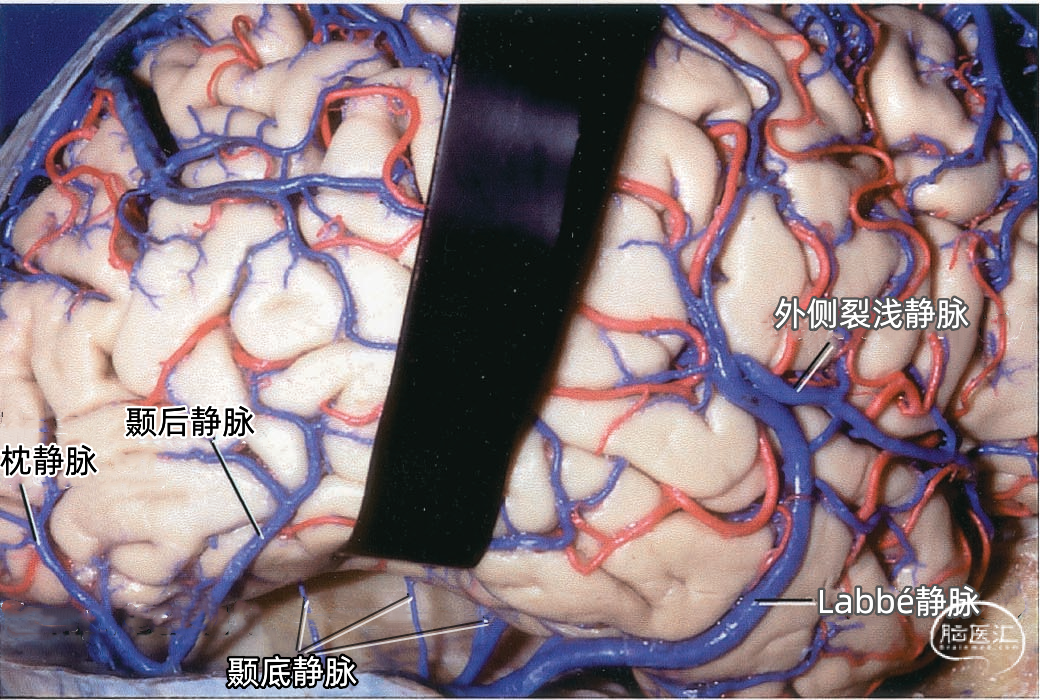

颞叶外侧面的皮层静脉可引流入横窦(上图),但在流入横窦之前,它们常向内沿颞叶底面进入小脑幕的短窦,此窦进入横窦末端之前在小脑幕内走行大约1cm。来自颞叶和枕叶底面的皮层静脉通常汇入外侧小脑幕窦。 Labbé静脉通常终于横窦(上图),但也可弧形围绕大脑半球下缘汇入外侧小脑幕窦。▼9.小脑幕窦

▼2.Labbé静脉

Labbé静脉也称下吻合静脉,是跨越颞叶外侧,连接外侧裂与横窦之间的最大吻合静脉。它通常起自外侧裂中部,行向后下,进入横窦前部。 Labbé静脉经过颞叶表面的位置有可能非常靠后甚至位于颞叶的最后界,或非常靠前达颞叶前1/3的外侧面。在此研究的20例半球中,12例Labbé静脉位于颞中静脉水平,6例位于颞后静脉水平,2例位于颞前静脉水平。有时会有两条Labbé静脉,其中后支通常会粗大一些。

下图示横窦和小脑幕窦的分支。抬起颞叶的后部,暴露进入横窦的Labbé静脉、颞后静脉和枕后静脉,从颞叶底面进入小脑幕窦的颞底静脉。

一些颞叶和枕叶凸面外侧的静脉并不直接注入横窦,而是转向内侧达颞叶底面汇入小脑幕窦。

颞叶静脉划分为:引流颞叶凸面的外侧组和引流颞叶底面的下组。 颞叶外侧组静脉还分为上升组,行向外侧裂。下降组,注入颞叶下方的静脉窦。上升组由颞外侧裂静脉组成,下降组由颞前、中、后静脉组成。 颞外侧静脉组及其引流区域如下:颞前静脉引流外侧面前1/3,颞上回除外;颞中静脉引流颞叶凸面中部;颞后静脉引流颞叶凸面后1/3,有时包括角回和顶叶前部;颞外侧裂静脉引流从颞极到外侧裂后端的颞上回。 颞下静脉分为:外侧组引流入小脑幕前外侧的窦;内侧组沿颞叶内侧缘,流入基底静脉。外侧组由前、中、后颞底静脉组成,颞底静脉好像放射状从枕前切迹发出,经过颞叶的下面。内侧组由钩回静脉、海马前静脉和颞叶内侧静脉组成。颞极附近基底面通常由颞外侧裂静脉引流。 颞下静脉及其引流区域如下:颞底前静脉引流颞底前1/3、颞枕回和邻近的海马旁回;颞底中静脉引流颞叶下面中1/3;颞底后静脉引流颞叶底面和枕叶前部;钩回静脉引流钩回和邻近的海马旁回:海马前静脉引流钩回后部和邻近的海马旁回;颞内侧静脉引流脑干上部旁基底池边缘的海马旁回。

小脑幕组(上图 绿色)的桥静脉汇入行经小脑幕的静脉窦,即小脑幕窦或小脑幕附近的横窦和岩上窦。本组静脉引流颞叶外侧面和底面、枕叶的底面,包括颞底静脉、枕底静脉和来自颞叶外侧面的降静脉,如Labbé静脉。 除Labbé静脉外,这些静脉虽然有可能进入横窦,但大多数围绕半球的下缘汇聚于枕前切迹到达外侧小脑幕窦。而Labbé静脉通常汇入横窦。大脑底面的桥静脉汇入静脉窦之前,经常粘连于与中颅窝底硬膜和小脑幕表面。 从外侧面引流入小脑幕窦的静脉包括颞前静脉、颞中静脉、颞后静脉和Labbé静脉。

在颞底的后方可能遇到许多桥静脉(下图),这些静脉包括颞、枕、颞底、枕底静脉和Labbé静脉,伤及这些从大脑半球下表面进入横窦和小脑幕窦的静脉,经常会产生某种程度的静脉梗塞和颞叶水肿。这些静脉闭塞以后,有可能导致对侧肢体偏瘫,其中面部和上肢较下肢更明显,优势半球受累还可能导致失语。 在横窦和岩上窦结合部抬起颞叶时经常遇见的难题是有许多来源于颞叶外侧面和底面的静脉聚集在这一区域(上图)。颞下入路手术后遗症的产生往往是因为Labbé静脉的闭塞;但是术中单纯烧闭Labbé静脉的情况并不多,因为当颞下入路需要在颞叶内侧暴露小脑幕缘时,也需要牺牲其他许多这一区域的桥静脉。